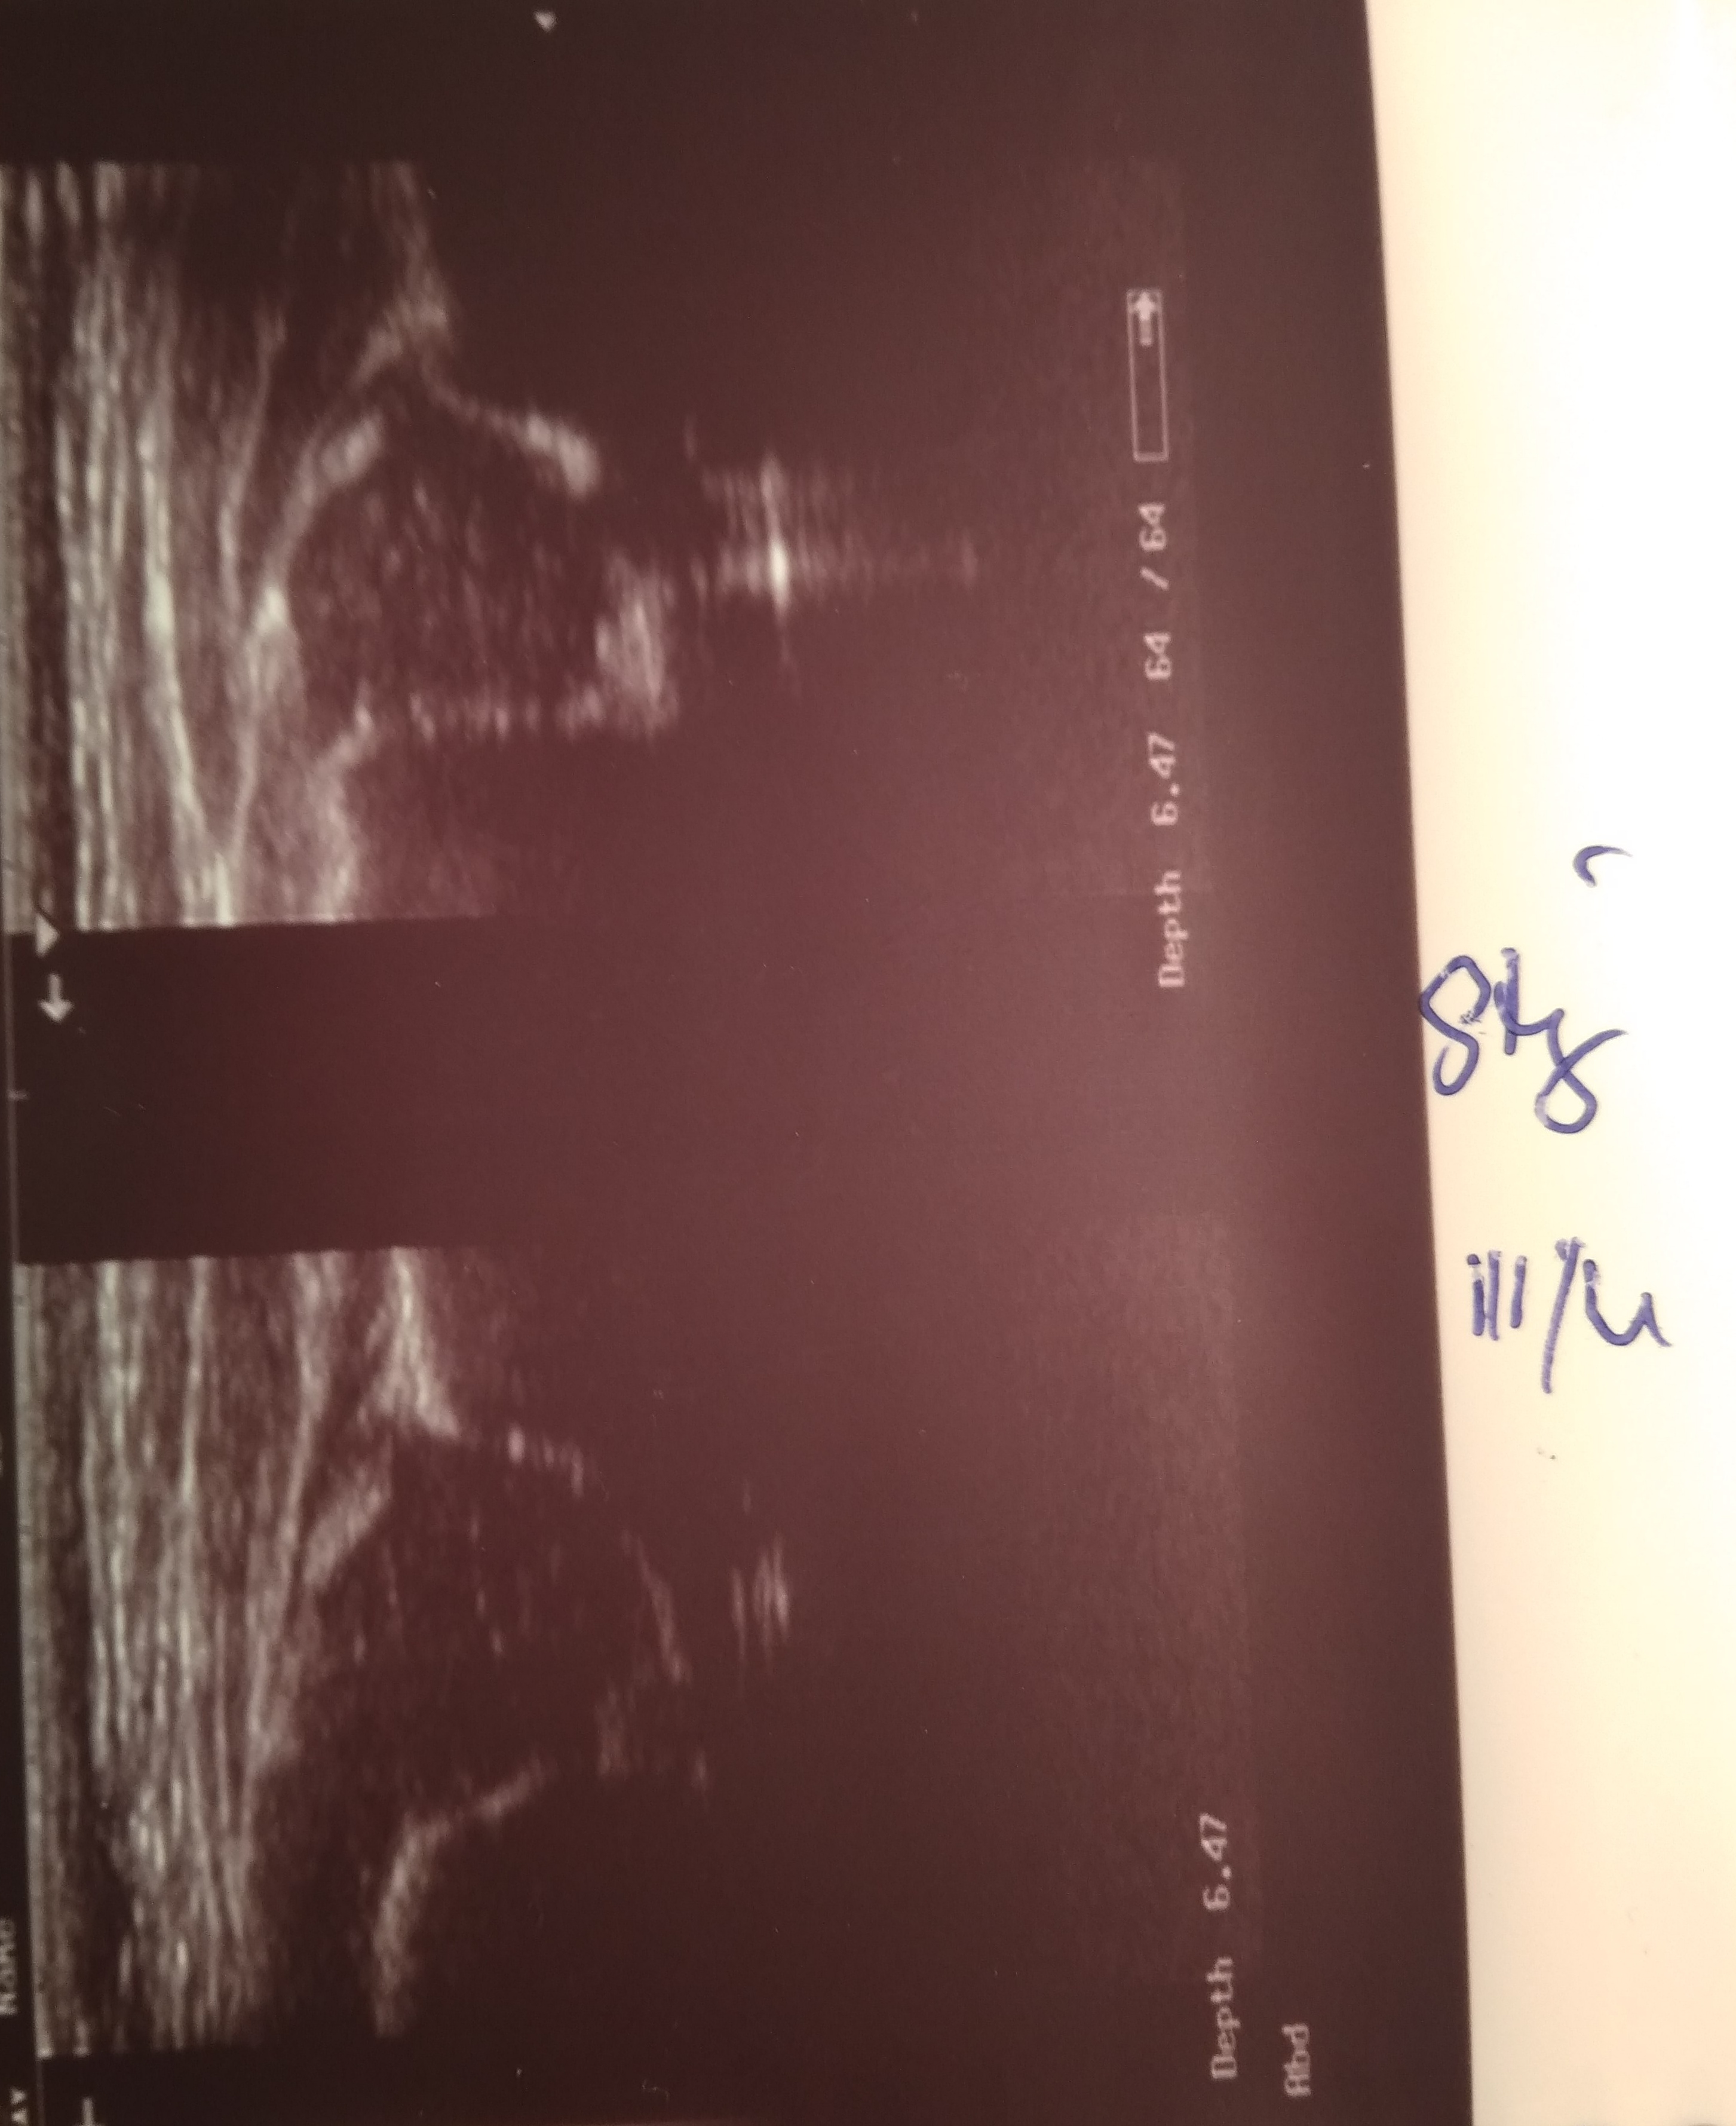

typ P :D L: III/IV biodra niestabilne obustronnie rozpoznana po porodzie na oddziale noworodkowym zlecono usg za dwa tygodnie (brak stadandartów postepowania) ;

7 dzien zycia środa dzien póżniej Typ P IIIa L D widac juz poprawe dalej profilaktyka kontrola w nastepnym dniu